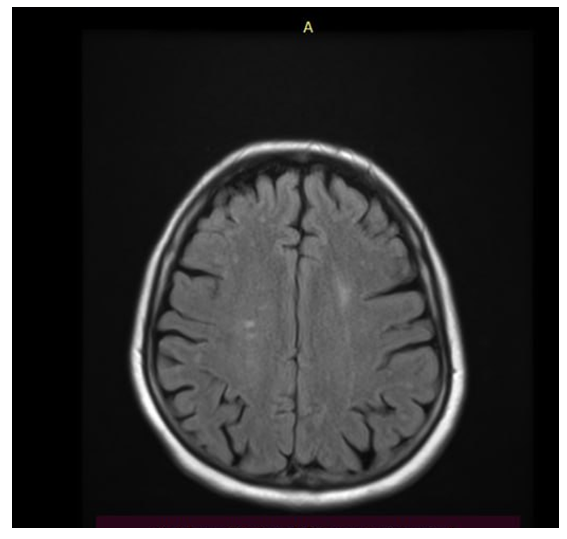

To objectively characterize brain damage in pregnant women with severe preeclampsia, magnetic resonance imaging (MRI) was performed using FSE_T2_FLAIR, T1_FLAIR, and DWI modes. The study was performed on axial, coronal, and sagittal sections with a 5-mm slice thickness.Brain MRIs (Figs. 1, 2) reveal areas of hyperintensity on FLAIR sequences, predominantly in the occipito-parietal regions of the white matter, with a tendency toward symmetrical distribution. These changes are characterized by vasogenic edema without signs of mass effect, midline displacement, hemorrhage, or ischemic injury. | Figure 1. MRI of the brain of patient Z.T., with severe preeclampsia (axial slice, FSE_T2_FLAIR mode): hyperintense foci of vasogenic edema in the occipital-parietal regions |

| Figure 2. MRI of the brain of the same patient: symmetrical areas of increased signal on FLAIR, characteristic of posterior reversible encephalopathy syndrome (PRES) |

The ventricular system is not dilated, the contours are clear, and the subarachnoid spaces are not deformed. On FSE_T2 and T1 FLAIR sections, the structure of the corpus callosum and brainstem is preserved, and no signs of focal necrotic changes are detected. Dynamic observation 10-14 days after delivery showed regression of foci of hyperintensity, confirming the reversible nature of the process.The obtained data indicate the presence of typical MRI signs of reversible posterior encephalopathy syndrome (Posterior Reversible Encephalopathy Preeclampsia Retinopathy Syndrome (PRES) occurs in patients with severe preeclampsia. This syndrome develops as a result of hypertensive crisis, endothelial dysfunction, and impaired cerebral blood flow autoregulation, leading to increased permeability of the blood-brain barrier and the development of vasogenic edema.Visualized areas of hyperintensity in the white matter of the parieto-occipital lobes reflect reversible perfusion disturbances. The absence of signs of cytotoxic edema and necrosis confirms the benign nature of the process, provided blood pressure is corrected promptly and delivery is performed.Correlation analysis showed a significant relationship between the severity of hyperintensive changes and hemodynamic parameters (r = 0.62; p < 0.01) and coagulation status (r = 0.58; p < 0.05), which reflects the systemic nature of vascular disorders in severe preeclampsia.Table 1 presents the data of the general blood test in pregnant women with severe (group 1a) and moderate (group 1b) preeclampsia compared to the control group.Table 1. Main indicators of general blood analysis in examined pregnant women (M ± m)  |

Summarizing all the data in our study, we can conclude that in pregnant women with severe preeclampsia, brain MRI reveals symmetrical hyperintense foci in the occipito-parietal regions, consistent with vasogenic edema. These changes are characteristic of posterior reversible encephalopathy syndrome (PRES), confirming the presence of systemic endothelial dysfunction and hypertensive CNS damage. Following stabilization of blood pressure and delivery, MR changes reverse, demonstrating the reversibility of cerebral dysfunction. Thus, the biochemical profile in pregnant women with preeclampsia of varying severity is characterized by increasing signs of multiple organ dysfunction as the disease worsens, consistent with clinical manifestations and MRI findings confirming the development of reversible encephalopathy.